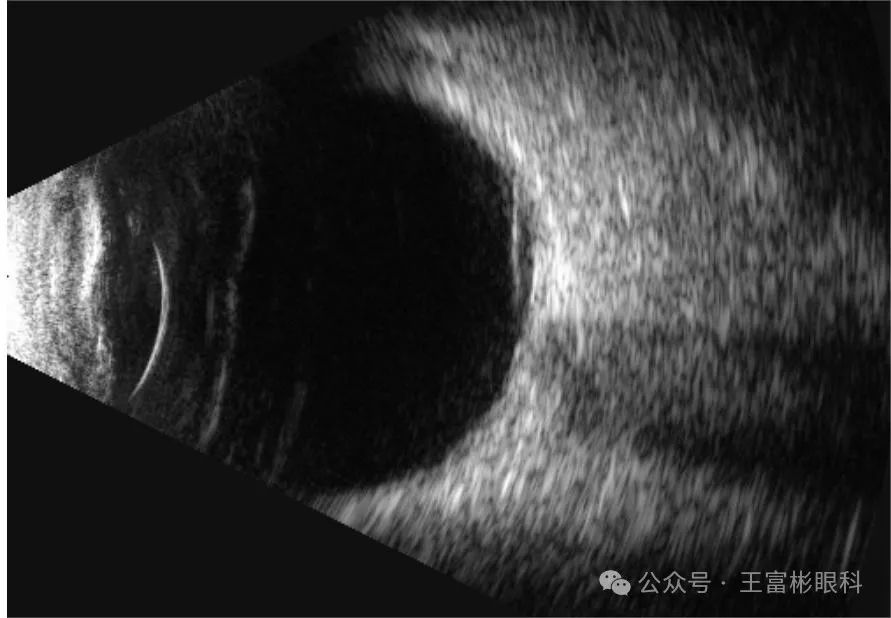

值得注意的是,鼻侧视网膜距离视盘大约8个视盘直径的地方,视网膜静脉出现了一个很大的血管袢,这个血管袢位于一片无灌注区之内。假如做一个点对点的分析,会发现对应于en face OCTA影像上血管袢的B-scan OCT影像,出现了“飞碟”形状的鲜红血流信号。这个B-scan血流信号,突入进玻璃体,并且得到了en face OCTA影像的佐证。

因为正常情况下,玻璃体是没有血管的,但这只眼睛的眼底在分割断层时,玻璃体层面明确显示了这个血管袢的存在。3D影像也证实了这一点。